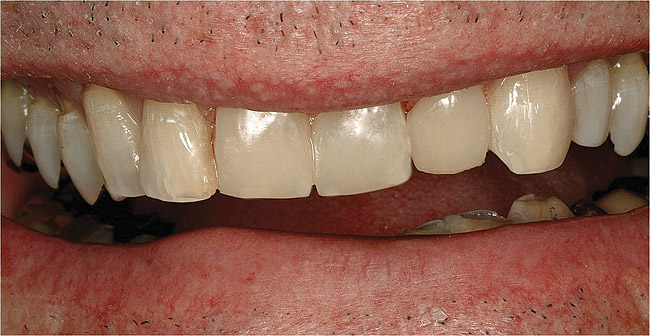

Figure  11  Loss of tooth enamel and translucency, resulting in yellowing of teeth.

Figure 11

Figure 12  Adhesive dentistry with resin-based composite.

Figure 12